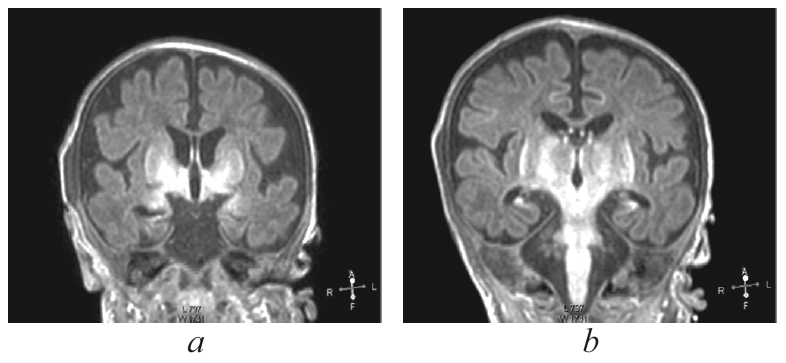

Рис. 2. Магнитно-резонансная томограмма головного мозга пациента, сагиттальный срез. Визуализируется гиперинтенсивный сигнал в области базальных ядер (тонкая стрелка), прецентральной извилины (толстая стрелка) / Fig. 2. Patients brain, magnetic resonance imaging, sagittal. Abnormal T1 hyperintensity is presented at the level of thalamic (thin arrow), motor cortex (thick arrow)

На 27-й день жизни выполнена МРТ головного мозга, диагностирована гипоксически-ишемическая энцефалопатия с двухсторонним поражением базальных ядер, ножек мозга, прецентральной извилины и гиппокампов. Кроме того, выявлена смешанная гидроцефалия по заместительному типу (рис. 1, 2). Визуализируется симметричное усиление МР-сигнала в области базальных ганглиев (рис. 1, а), гиппокампов (рис. 1, b), также определяется значительное расширение субарахноидальных пространств, преимущественно над лобными, височными долями больших полушарий с расширением сильвиевой щели, расширение борозд и истончение коры больших полушарий (наружная гидроцефалия по заместительному типу), расширение передних отделов боковых желудочков.